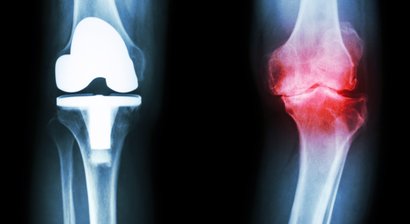

Knieprothese

Arthrose im Kniegelenk (Gonarthrose) führt bei Betroffenen mit der Zeit zu starken Schmerzen und massiven Bewegungseinschränkungen. Die Gelenkerkrankung ist durch einen Abbau des Gelenkknorpels charakterisiert und kann vor allem zu Beginn gut mithilfe konservativer Maßnahmen (z.B. Ph...